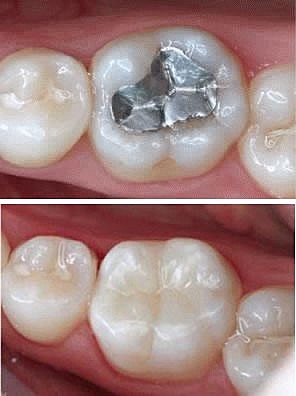

• Cambio amalgamas.

Cambio amalgamas.

Cambio de amalgama por resina OD. 1.7, 1.5, 1.6.

Cambio de amalgamas por resinas OD. 1.4, 2.5. 2.4